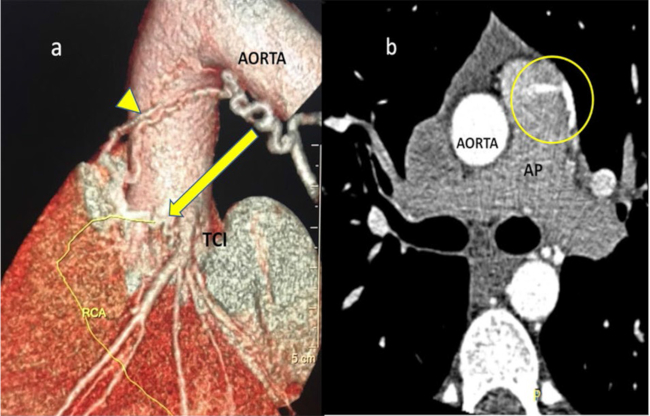

Ante la sospecha de una anomalía vascular se solicitó una tomografía cardíaca que confirmó el hallazgo de una comunicación arterial o “fístula coronaria” compleja, con origen en el tercio distal del tronco de la coronaria izquierda (TCI) (Figura 2a, flecha), luego una anastomosis con una rama bronquial anómala (Figura 2a, punta de flecha) y, finalmente, el drenaje de ambas mediante un tronco común en la arteria pulmonar (Figura 2b, círculo). La fistula coronaria tiene una prevalencia de 0,7-1% en la población general, el trayecto coronario-pulmonar es el más frecuente, sólo 3% de los hallazgos corresponden a fístulas complejas. 1 Actualmente no hay un protocolo para su manejo clínico en deportistas; si está asintomático y sin evidencia de isquemia, se recomienda su seguimiento. 2